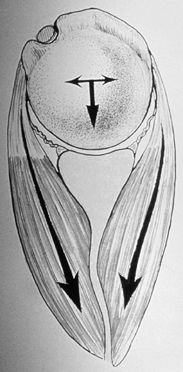

consisting of the teres minor, infraspinatus, supraspinatus, and

subscapularis muscles. These muscles encircle the glenohumeral joint,

and their insertion sites are broadly intermeshed with the underlying

joint capsule (29,32,34).

These intrinsic muscles have relatively short lever arms and pass close

to the axis of rotation of the joint. As a result, they act more as

primary stabilizers than as primary movers of the glenohumeral joint.

The net effect of contraction of the rotator cuff muscles is to create

a compressive load across the glenohumeral joint. This load steers the

humeral head into the glenoid fossa, creating the concavity-compression

mechanism (Fig. 80.7) (14,17,71,88,125,135,161).

![]() |

|

Figure 80.7. The dynamic stability provided by the rotator cuff muscles produces a concavity-compression mechanism.